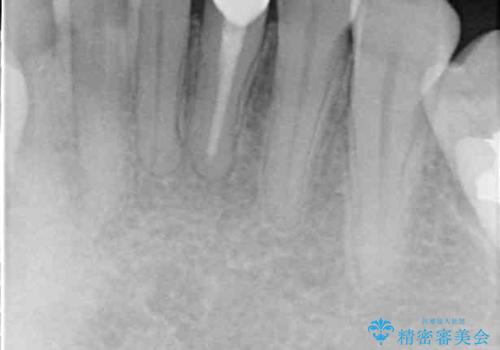

初回の根管治療後には痛みが速やかに改善し、6か月後のレントゲン写真では根尖の病変が消失していることが確認できました。

根管治療を行った後にオールセラミッククラウンにて補綴することとしました。